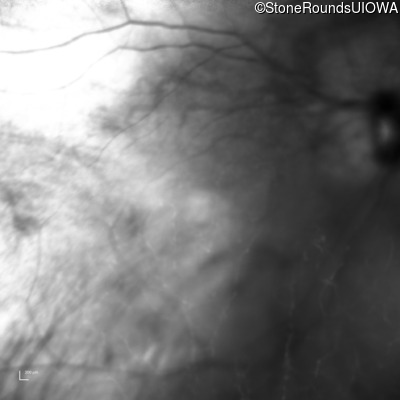

Age at visit: 41 years (Visit 2)

OD OS

This 41 year old woman was highly myopic as a child and experienced a rhegmatogenous retinal detachment OS at age 20.

The clinical features favoring the diagnosis of Sticker syndrome in this patient include extensive radial lattice degeneration, a personal and family history of rhegmatogenous retinal detachment, a history of cataract surgery before age 30 (and very high myopia before that), arthritis in her knees and hips and a slightly flattened mid-face.